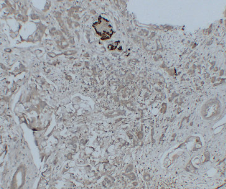

GCG Mouse Monoclonal antibody[2F9D9]

IHC    1/200-1/400